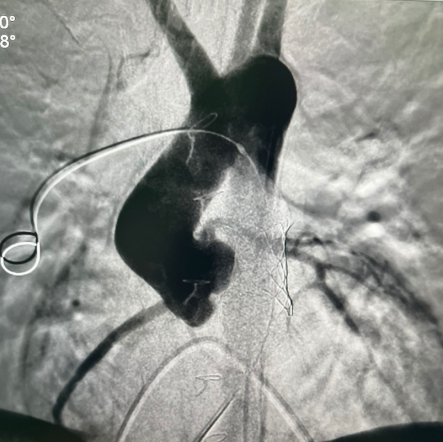

Как пояснил заведующий кардиохирургической службой клиники Педиатрического университета Андрей Нохрин, у Максима из ЛНР был врожденный стеноз аортального клапана. В 2009 году ребёнку провели баллонную дилатацию – расширили просвет клапана аорты с помощью специального катетера. Спустя год процедуру потребовалось повторить. В 2014 мальчику выполнили операцию Росса – заменили аортальный клапан собственным лёгочным клапаном. На место клапана лёгочной артерии имплантировали так называемый кондуит – трубку с клапаном из специальных материалов – дакрона и гортекса.

В 2021-м у пациента развился стеноз клапансодержащего кондуита, но врачи смогли разрешить ситуацию методом баллонной ангиопластики. Однако в последующие годы вновь возник стеноз в этой же зоне, что привело к повышению давления в правых отделах сердца и сердечной недостаточности. Ребёнку требовалось высокотехнологичное лечение, и в ходе консилиума под руководством ректора СПбГПМУ Дмитрия Иванова было принято решение о госпитализации Максима в федеральную клинику вуза.

У пациента из Луганской Народной Республики просвет ранее имплантированного кондуита составлял 1,5 сантиметра, поэтому рентгенхирурги на первом этапе расширили его методом баллонной дилатации. При этом был риск разрыва сосуда, поэтому, чтобы избежать возможных осложнений, медики сначала имплантировали стентграфт – металлический каркас, покрытый герметичным полимером. Просвет кондуита удалось расширить до необходимого диаметра. Затем через бедренную вену хирурги доставили к сердцу искусственный биологический клапан лёгочной артерии Myval индийского производства.